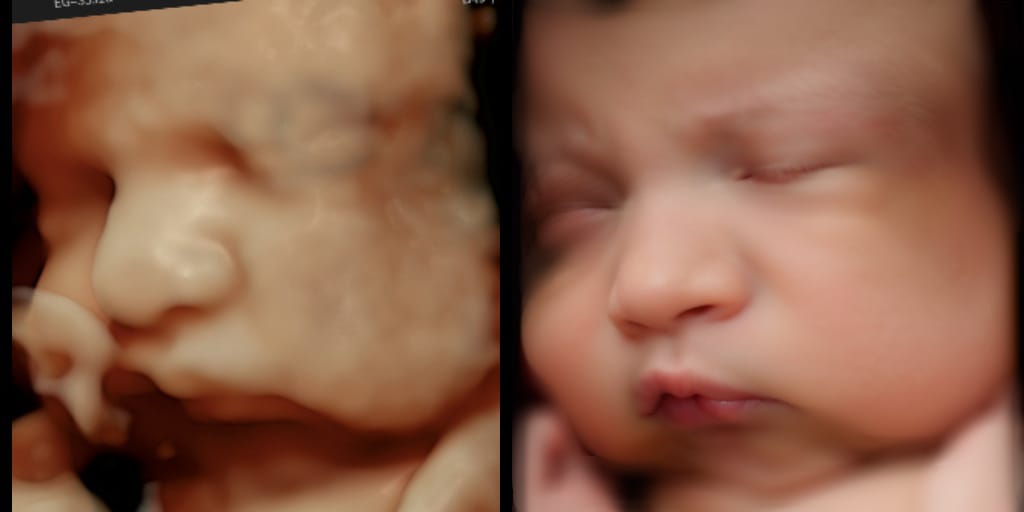

Se trata de Beia, un sistema que recopila miles de imágenes tridimensionales para crear representaciones realistas del bebé. Más allá de su valor clínico, esta herramienta tiene un profundo impacto emocional, fortaleciendo el vínculo entre madre e hijo incluso antes del nacimiento.

El Dr. Viñals les explicó, tras el examen, que Borja sería uno de los primeros bebés en contar con una imagen generada por este sistema. “Nos dijo que estaban probando un software de inteligencia artificial que muestra cómo se vería el bebé al nacer. Borja sería uno de los primeros en acceder a esta tecnología y la imagen que vimos era un prototipo de cómo se vería al momento de nacer”, señala.

La experiencia fue impactante para toda la familia. “Revisamos la imagen cuando salimos de la consulta y nos sorprendimos, porque la verdad es que parecía demasiado real. Entre nosotros nos preguntábamos si de verdad Borja iba a ser así. Y la sorpresa fue que sí: el color de las pestañas y la forma de su cabeza, su pelo claro, la nariz, la boca son muy parecidos a los que tiene hoy”.